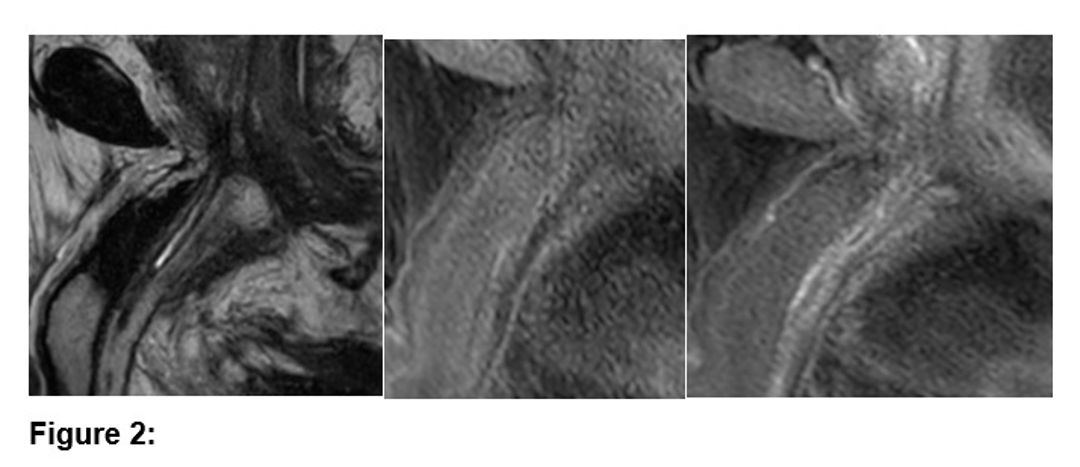

Figure 1

1.	Case 1: A 62-year-old male with recurrent urethral strictures after-coronary bypass surgery and internal urethrotomy. MRI revealed complete occlusion of the distal prostatic urethra and partial stenosis in the proximal bulbous urethra. Anastomotic urethroplasty was successfully performed, excising a 2 cm fibrotic segment.

2.	Case 2: A 63-year-old male post-liver transplant with a recurrent obliterative urethral stricture. MRI and retrograde urethrography confirmed a 2.5 cm stricture in the bulbous urethra, leading to an end-to-end anastomotic urethroplasty after excision of the stricture.

3.	Case 3: A 58-year-old male with a complex stricture, thought to be post-traumatic, was diagnosed with a non-traumatic obliterative stricture. MRI identified a 7 mm stenotic segment in the distal penile urethra. Urethroplasty was performed, addressing the complex stricture with an appropriate surgical approach.

The case series involved three male patients, aged 58 to 63 years, who had non-traumatic obliterative urethral strictures and were managed using MRI for preoperative evaluation. MRI was performed according to the “Joshi protocol,” which involves the use of an alpha-blocker to ensure adequate bladder neck opening, followed by sterile saline injection through a cystostomy (if present) and lignocaine gel for urethral administration. This technique has been shown to provide more accurate depictions of the urethral gap compared to conventional urethrography. All patients gave informed consent for their data to be used. MRI sequences included T2-weighted and post-contrast T1-weighted images to assess the urethral and periurethral anatomy, including spongiofibrosis and fibrosis-related changes.

The results emphasize the role of MRI in providing detailed and reliable anatomical information for complex non-traumatic obliterative urethral strictures. In each case, MRI effectively identified the location, length, and extent of the strictures, which were critical in planning the surgical approach. MRI was particularly useful in detecting fibrosis and soft tissue involvement that might not have been fully visible with traditional methods like retrograde urethrography. Moreover, MRI was essential in guiding surgeons to perform appropriate urethroplasty techniques, such as end-to-end anastomotic repairs, thus improving surgical outcomes.